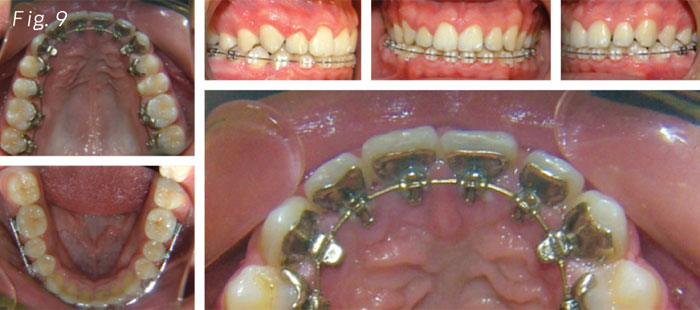

When the upper braces arrived it was very easy for the patient to make the transition from the Essix .040 with turbos to the customized lingual braces with turbos on cuspids (Fig. 9).